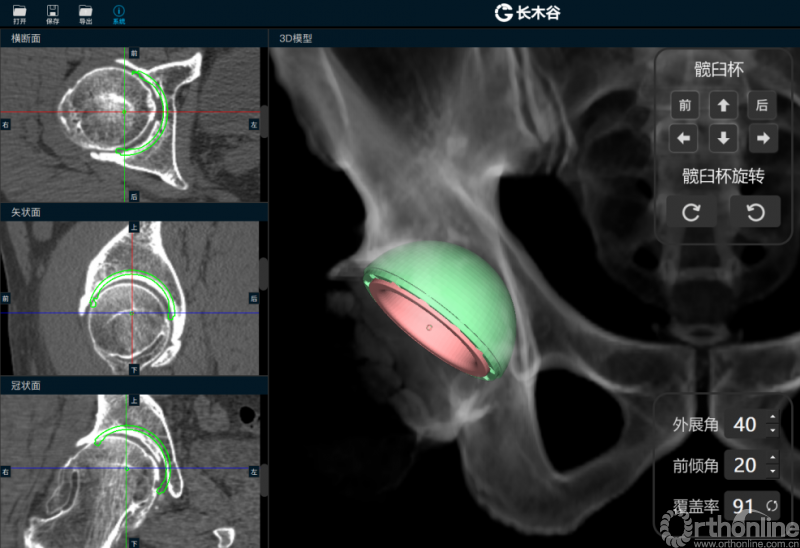

AI HIP系统智能安放54mm直径的强生Pinnalce髋臼杯

最后,AI HIP系统根据患侧股骨颈干角、偏心距偏大的特殊情况,智能选择使用高偏高颈干角假体,对下肢等长和等偏心距重建做出了精准设计。根据系统预测结果,术中使用54mm Pinnalce髋臼杯、12号CORAIL高偏股骨柄、36mm 陶瓷股骨头、小转子上23mm截骨,实现髋关节的个体化、精准化重建。